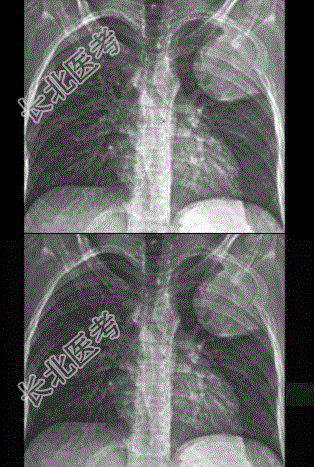

- 单项选择题女性,27岁。发热, 左侧胸部疼痛2个月余,结合影像学检查, 最可能的诊断是

A、骨肉瘤

B、肺癌

C、软骨肉瘤

D、骨样骨瘤

E、尤因肉瘤